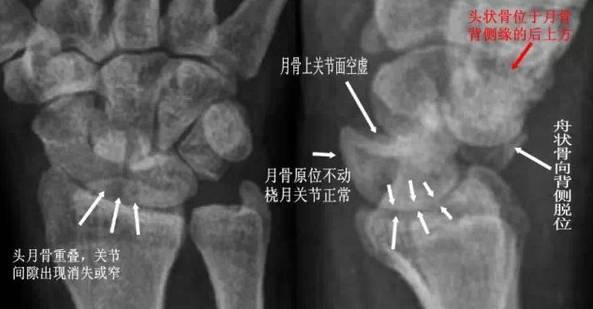

(2) 经舟骨月骨脱位:除月骨脱位外,同时伴有舟骨骨折,且骨折近段随月骨一起向前脱位,骨折远段仍处于原位置。

△ 经舟骨月骨脱位影像特点

(3)月骨周围脱位:表现为腕关节缩短,头骨与桡骨距离变近,头骨、钩骨与月骨部分重叠,月骨形态及位置基本正常。

△ 月骨周围脱位影像特点